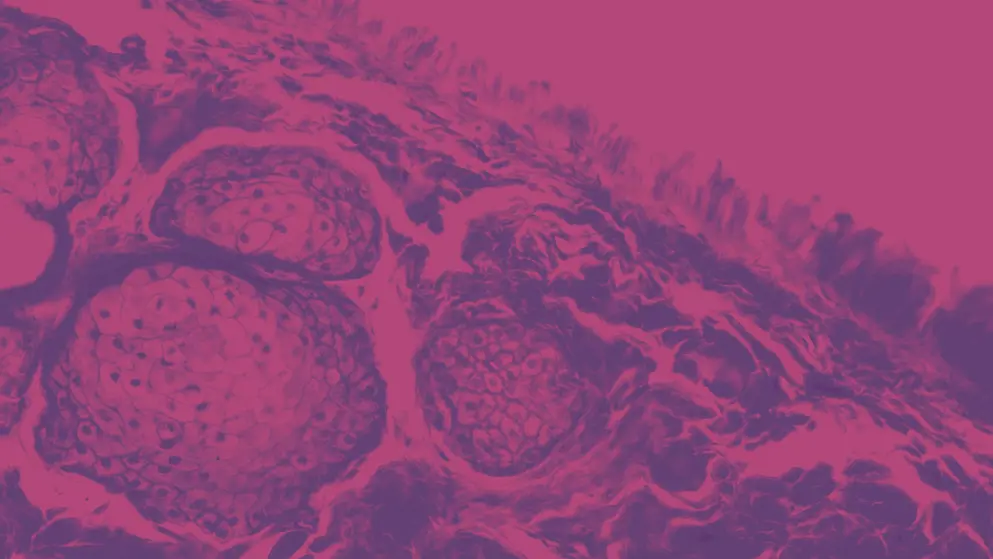

How much do you know about glaucoma? Enhance your knowledge of this disease of global concern.

This expert-reviewed Learning Zone contains a wealth of educational material designed to strengthen your knowledge of glaucoma. It contains information and resources on glaucoma risk factors, the unmet needs for diagnosis, strategies for screening and diagnosis, and treatment options. You will also learn about the increasing prevalence and burden of the disease.

Find out the signs, symptoms and risk factors for glaucoma so you can screen people who are at greatest risk. Earlier diagnosis can lead to earlier treatment and preserve vision, helping prevent irreversible blindness.